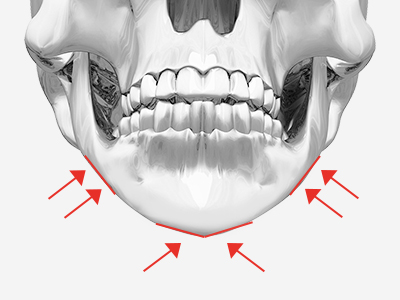

如果將我們的臉比作球,如圖所示,耳下方輪廓不是從正面看最寬的部位,而比最寬部位靠後。

因此除了耳下方輪廓外翻的少數情況,下頜角切除術不會縮小下頜寬度。

WIAD方下巴縮小術透過將皮質整體切除(full thickness corticectomy),實現最卓越的正面改善效果。

如果將我們的臉比作球,如圖所示,耳下方輪廓不是從正面看最寬的部位,而比最寬部位靠後。 因此除了耳下方輪廓外翻的少數情況,下頜角切除術不會縮小下頜寬度。 WIAD方下巴縮小術透過將皮質整體切除(full thickness corticectomy),實現最卓越的正面改善效果。

下頜角切除術

切除下頜角時,切除部位從正面看角度不夠明顯。